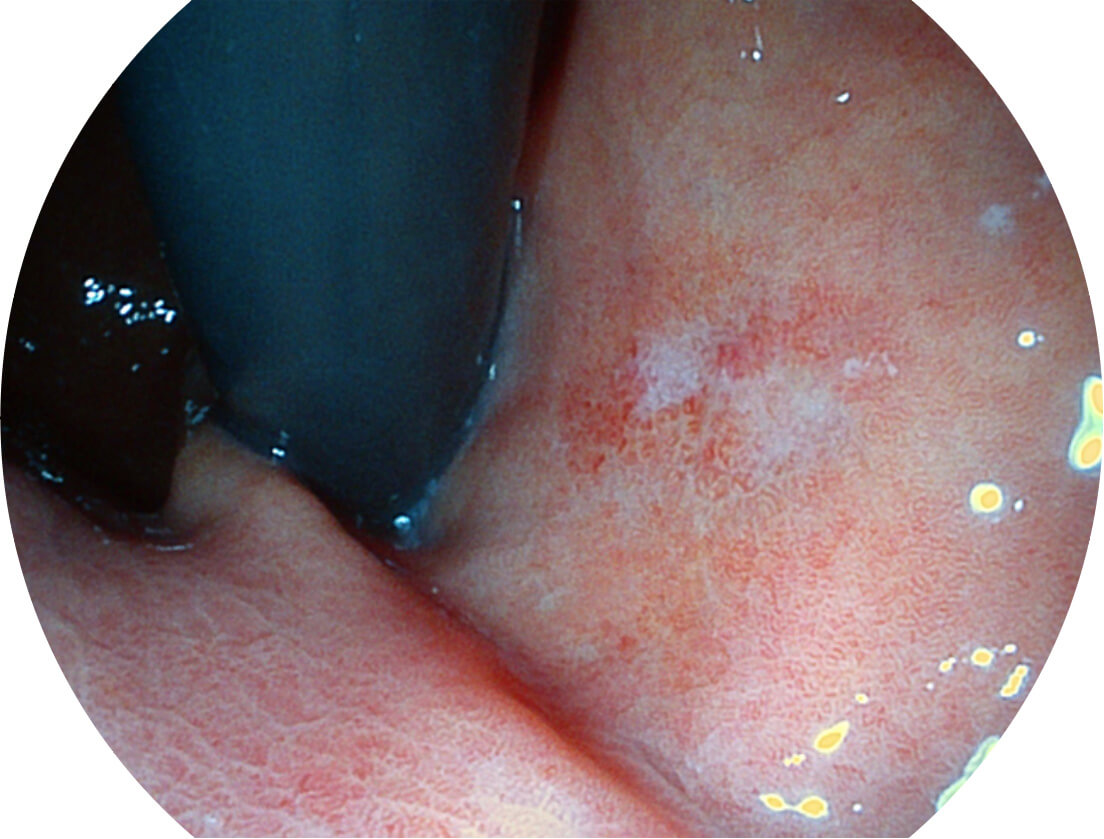

Versatile Intelligent Staining Technology, VIST

强调浅层黏膜结构的同时,保证照明亮度和提升浅层微血管与中层血管颜色对比度,病变边界更清晰。

白光图像

VIST图像

采用光路合束技术,光谱自由度高,实现了更丰富的照明模式,染色模式SFI及VIST,从远景到近景,助力消化道早期疾病诊断。